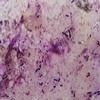

2.本病主要病理改變為腸壁小動脈內類纖維蛋白沉著、栓塞而致小腸出血和壞死。病變部位以空腸及迴腸為多見且嚴重;有時也可累及十二指腸、結腸及胃;少數病例全胃腸道均可受累。病變常呈節段性,可局限於腸的一段,也可呈多發性。病變常起始於黏膜,表現為腫脹、廣泛性出血,皺襞頂端被覆污綠色的假膜,但病變與正常黏膜分界清楚。病變可延伸至黏膜肌層,甚至累及漿膜。病變腸壁明顯增厚、變硬、嚴重者可致腸潰瘍和腸穿孔。鏡下可見病變黏膜呈深淺不一的壞死改變,輕者僅及絨毛頂端,重者可累及黏膜全層。黏膜下層除有廣泛出血外,亦可有嚴重的水腫和炎症細胞浸潤。肌層及漿膜層可有輕微出血。腸平滑肌可見腫脹、斷裂、玻璃樣變及壞死。血管壁則呈纖維素樣壞死,也常可有血栓形成。腸壁肌神經叢細胞可有營養不良性改變。除腸道病變外,尚可有腸系膜局部淋巴結腫大、軟化;肝臟脂肪變性、急性脾炎、間質性肺炎、肺水腫;別病例尚可伴有腎上腺灶性壞死。